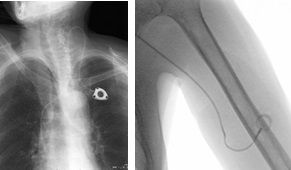

ポートの埋め込み

常時、点滴等を使用した治療を行う方に対して、針刺しの苦痛を軽減するためにポートを皮下に埋め込みます。その他に上肢の細くなった血管を小さな風船で内側から広げる治療も行っています。